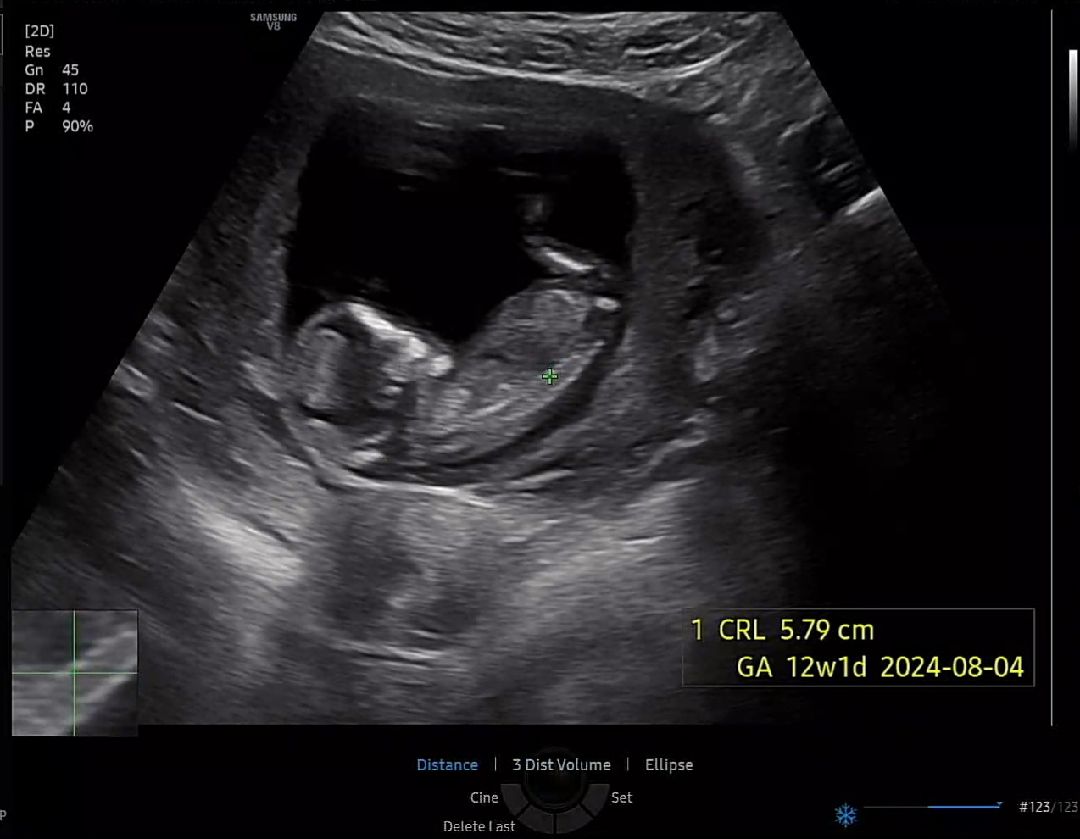

12주 각도법 성별 봐주세요!!

12주 2일이구요 오늘 초음파예요!!

이사진으로는 안보여용